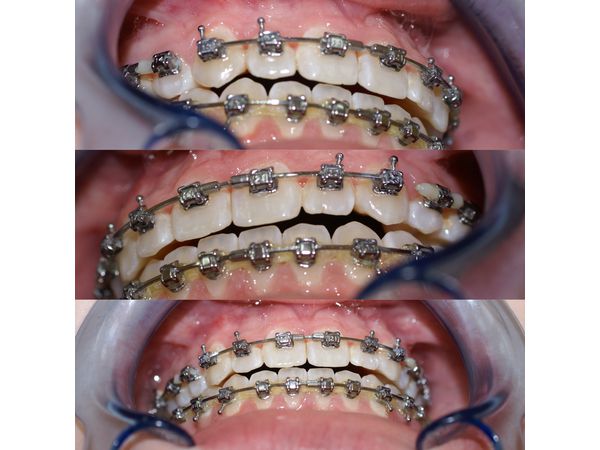

Прикус исправляли с помощью брекет-системы с двумя межкорневыми минивинтами снизу, без расширителей.

Судя по молярам, верхние боковые зубы сместились вперёд, как при II классе прикуса, поэтому было решено расширить зубной ряд и вернуть боковые зубы на место с помощью пружин, которые отталкивали моляры от верхних клыков.

При этом верхние клыки удерживали на месте в передне-заднем направлении и опускали вниз с помощью эластиков, которые крепились к межкорневым минивинтам, установленным за нижними шестыми молярами. Таким образом зубные ряды приближались друг к другу, закрывая прикус.

Также пациентке установили сегментированную дугу, чтобы подтянуть верхние резцы с клыками к нижнему зубному ряду. Дугу при этом зафиксировали, чтобы она не мешала прикусу.

В процессе лечения наблюдение проводили раз в полтора месяца.

На одном из этапов межкорневой минивинт слева потерял стабильность и его извлекли. Заново минивинт не устанавливали, так как достигнутого результата было достаточно.